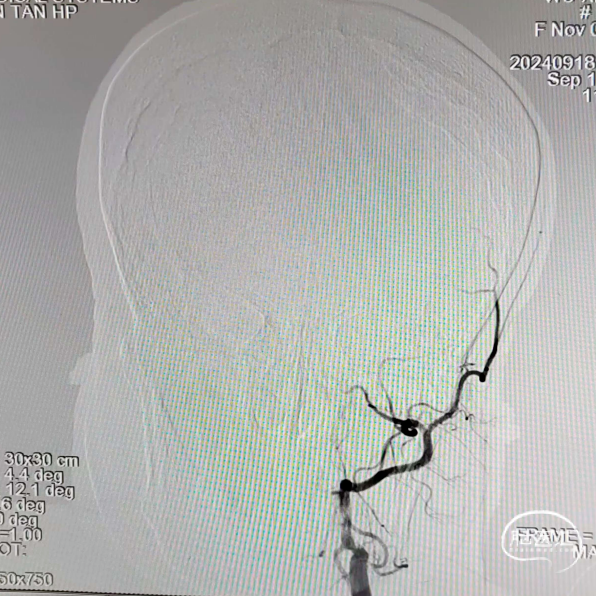

术前造影

RVA正位

RVA侧位

LVA正位

LVA侧位

LCA正位

LCA侧位

沿泥鳅导丝送入5F多功能携带8F导引导管至左侧颈内动脉C1段闭塞处,撤出泥鳅导丝及多功能导管,进行造影。

在路径图下,沿导引导管同轴技术送入微导丝(Command ES 0.014inch 300cm)带Rebar 18微导管至左侧颈内动脉C1段闭塞处,应用微导丝多次尝试成功通过闭塞处,撤出Command交换为Transend微导丝送至大脑中动脉远端。

微导丝、微导管到位后造影,证实微导管位于真腔内。

撤出微导丝,在微导管引导下将5.0*35mm Syphonet®取栓支架送至左侧大脑中动脉M1段,防止血栓逃逸,起到保护作用。

撤出微导管,沿5.0*35mm Syphonet®取栓支架导丝送入2.0*20mm Emerge球囊到达左侧颈内动脉闭塞段远端,充盈球囊至8atm,抽瘪球囊,从远端开始球囊扩张,直至颈内动脉起始处。

造影见左侧颈内动脉再通,恢复血流,前向血流良好,但血管管腔可见血栓。在微导丝及微导管引导下通过8F导引导管送入0.058inch 115cm 中间导管到位后,开始抽吸血栓,未见明显血栓抽出,给予替罗非班(6ml/h)。

造影可见颈内动脉C1段仍有狭窄,退出中间导管,在8F导引导管内沿5.0*35mm Syphonet®取栓支架导丝植入一枚Wallstent支架(9.0*50mm)。

再次造影时发现最狭窄处狭窄改善不满意,再经5.0*35mm Syphonet®取栓支架导丝引导下送入2.5*20mm Emerge球囊,在支架内给予球囊扩张。

最后将8F导引导管撤至左侧颈总动脉,造影可见左侧颈内动脉血流通畅,前向血流III级,远端各分支显影良好。